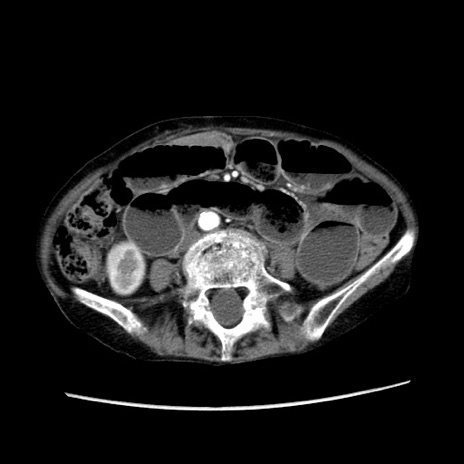

症例25(横断像)

【症例】80歳代女性

【主訴】胸のつかえ感

【現病歴】約9時間前に食後から胸のつかえた感じあり、嘔吐あり、来院。

【既往歴】胃癌(全摘)、胆摘、虫垂炎

【身体所見】心窩部に圧痛あり、反跳痛なし。

【データ】WBC 5700、CRP 0.05